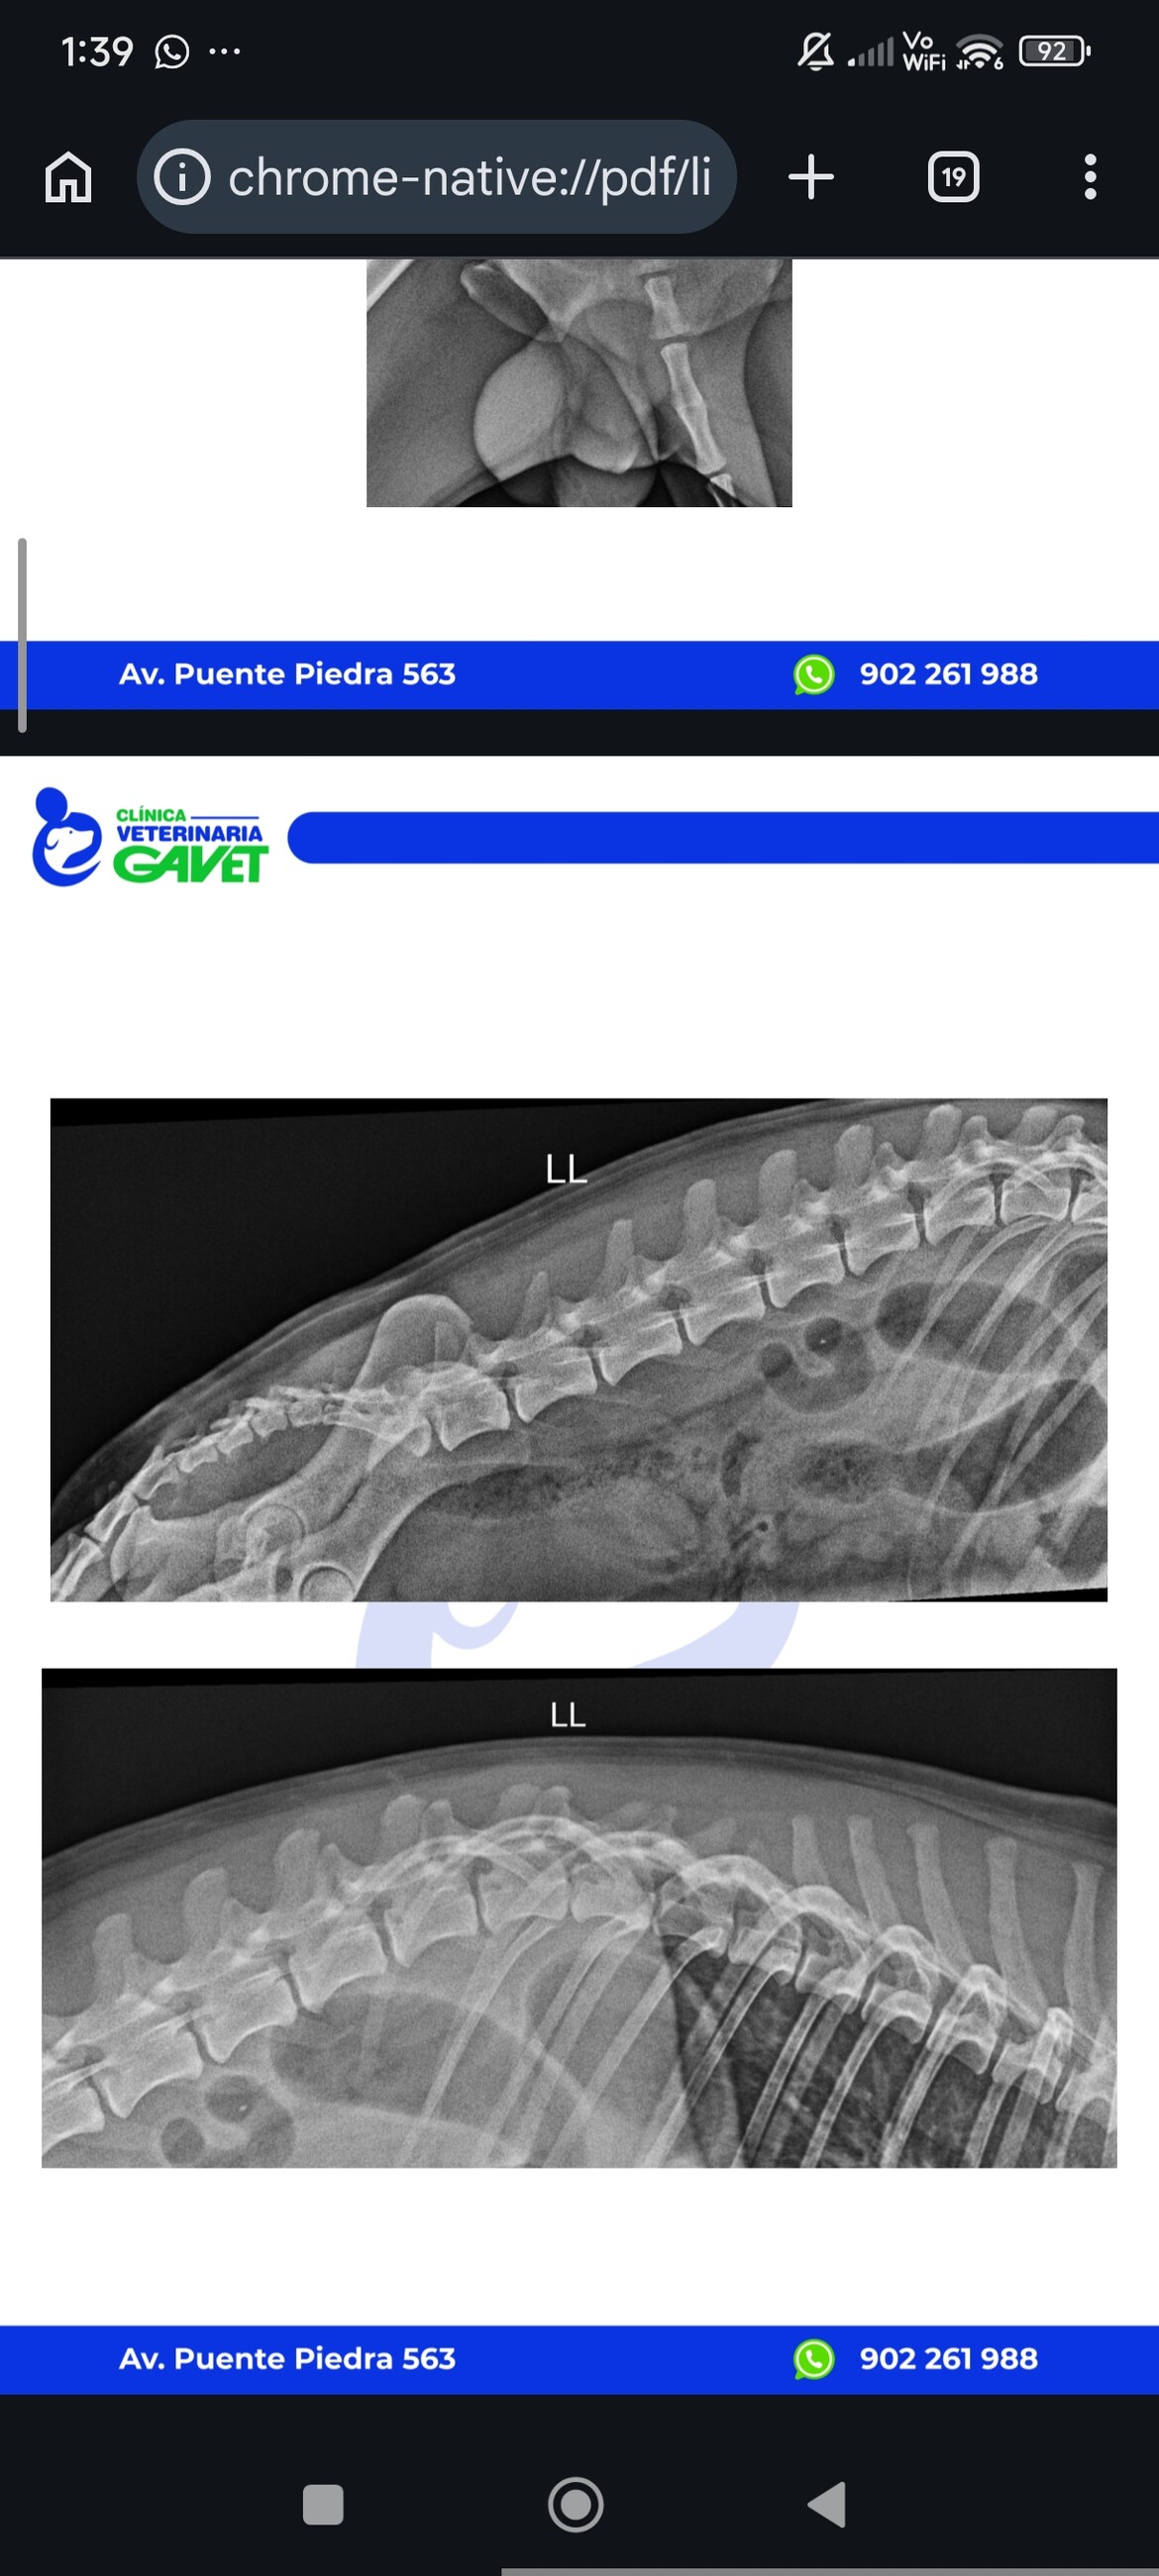

04/04/2026 Balu had an accident and has problems with walking 🥺

He is receiving a treatment for now for Inflammation - he doesn't have any bones broken. But still has problems with walking properly

he had today 06/06/2026 his appointment with a specialist neurologist.

Yesterday he couldn't walk/stand on both rear legs.

Today he can use his rear left leg.

Right rear leg while he is trying to walk/stand stays "straight", after he sit down or rest his leg is relaxed - doctor says it is a good sign that probably he can regenerat - because neuro signals change - (his leg doesn't stay all the time straight)

He needs to have TL MRI scan (Resonancia Magnética) to be sure if he doesn't need an operation to be able to walk. We hope he will be walking - Doctor says it is possible with quick reaction and rehabilitation plus medicine and we hope no operation well be needed. But ow will be sure after MRI scan